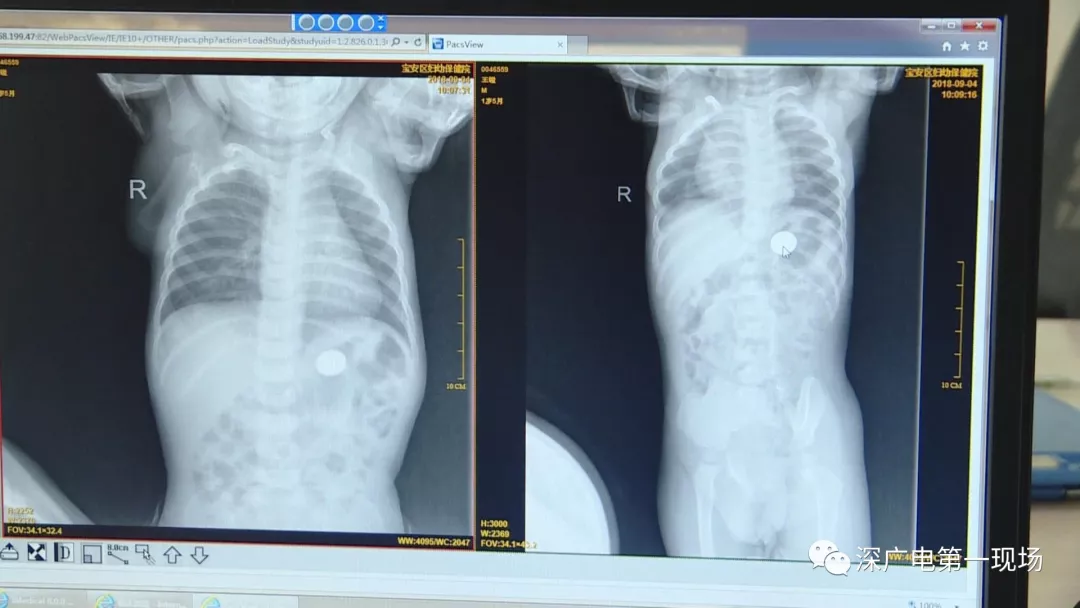

9月4號,一名1歲零5個月的男嬰因在家中摔傷,被父母送到了寶安區(qū)婦幼保健院,醫(yī)生診斷為左側(cè)尺橈骨骨折。在進行全麻手術(shù)之前,院方例行對嬰兒進行了周身檢查。手術(shù)前,兒外科醫(yī)生趙冠聰在查看患者的胸片時,發(fā)現(xiàn)這名嬰兒的胃部有一枚硬幣大小的暗影。

在與多名醫(yī)生會診之后,醫(yī)生擬定了聯(lián)合手術(shù)方案。

胃部取出一角硬幣

已吞咽半月之久

經(jīng)過兩個小時的時間,兒科醫(yī)生郭景濤為患兒取出了藏在胃底的一角錢硬幣。目前,患兒已經(jīng)痊愈出院。